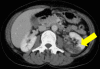

Case presentation: We report a case of a 55-year-old Japanese woman who had native valve endocarditis with L. garvieae. The case was complicated by renal infarction, cerebral infarction, and mycotic aneurysms. After anti-microbial treatment, she was discharged from the hospital and is now well while being monitored in the out-patient clinic.